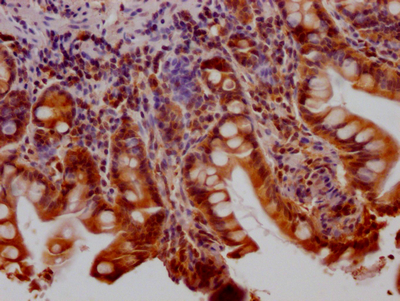

IHC image of CSB-RA802195A0HU diluted at 1:100 and staining in paraffin-embedded human small intestine tissue performed on a Leica BondTM system. After dewaxing and hydration, antigen retrieval was mediated by high pressure in a citrate buffer (pH 6.0). Section was blocked with 10% normal goat serum 30min at RT. Then primary antibody (1% BSA) was incubated at 4℃ overnight. The primary is detected by a Goat anti-rabbit IgG polymer labeled by HRP and visualized using 0.05% DAB.